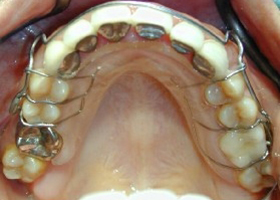

4.使用活動式矯正裝置矯正中(矯正方式因人而異)。

proimages/case/cosmetic/pic_case-025.jpg